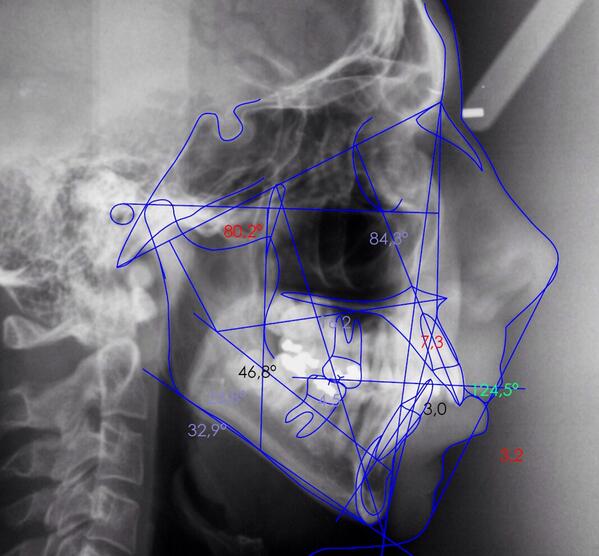

Ortodoncia

Alineamos tus dientes con tecnología avanzada para resultados naturales.

Galería

Sonrisas reales y tecnología en acción